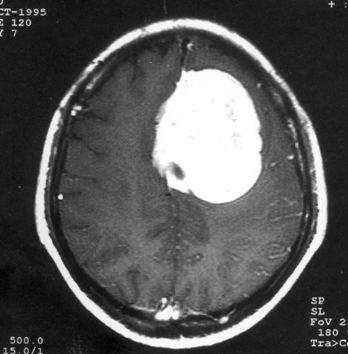

问题 病历摘要:??患者,男,40岁。发作性左下肢抽搐1年余,每次发作3~5分,每周发作1~2次。每次发作后感左下肢乏力,约半日后可自行恢复。既往身体健康。体检:神清,头顶部偏右有局限性骨性隆起(1.5×1.5cm),左鼻唇沟稍浅,伸舌居中。感觉、运动无明显异常。左浅反射减退,左下肢腱反射稍亢进,左Babinski征(-)。 下列关于脑膜瘤的叙述哪些是错误的?

选项 A.脑膜瘤大部分起源于蛛网膜细胞 B.多见于儿童 C.常使邻近的颅骨破坏或增生 D.可同时接受来自颈外、颈内或椎动脉系统的双重供血 E.呈浸润性生长 F.瘤周脑组织水肿一般比较明显 G.CT或MR增强扫描中强化一般不均匀 H.供血一般比较丰富